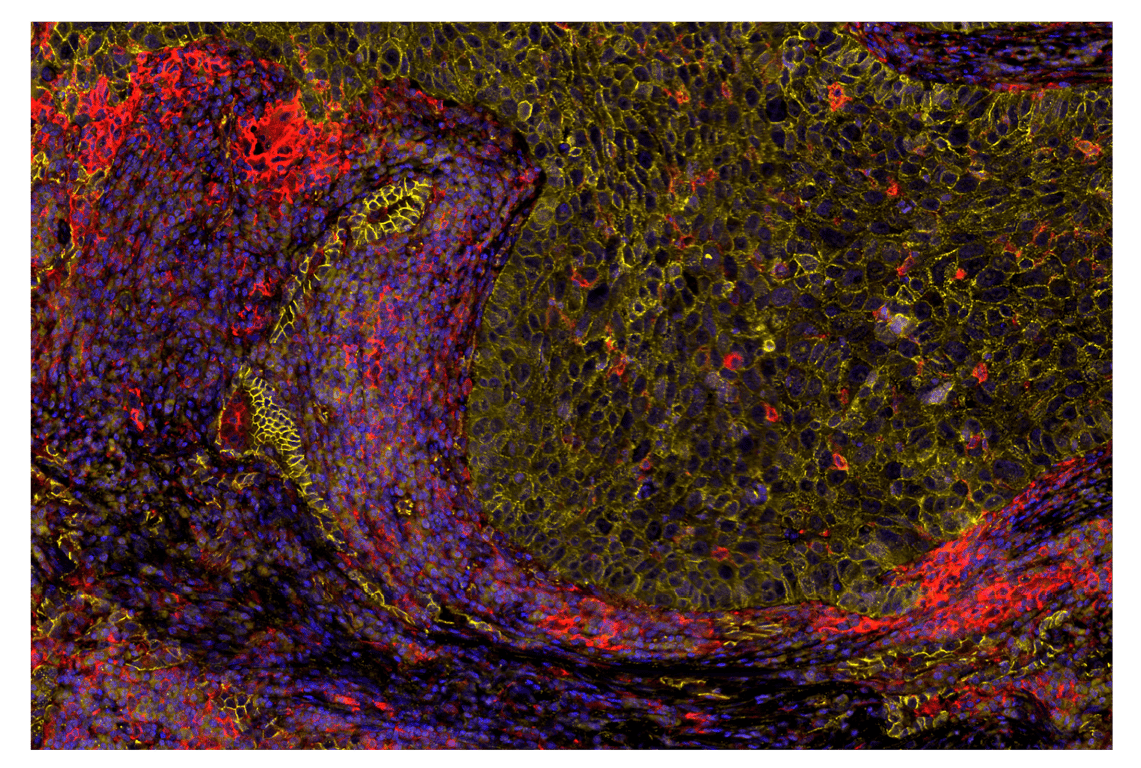

SignalStar™ multiplex immunohistochemical analysis of paraffin-embedded human non-small cell lung carcinoma using β-Catenin (D10A8) & CO-0108-647 SignalStar™ Oligo-Antibody Pair #25901 (red), Ki-67 (8D5) & CO-0014-594 SignalStar™ Oligo-Antibody Pair #35330 (yellow), and DAPI #4083 (blue). All fluorophores have been assigned a pseudocolor, as indicated.

Immunohistochemistry Image 1: beta-Catenin (D10A8) & CO-0108-750 SignalStar<sup>™</sup> Oligo-Antibody Pair